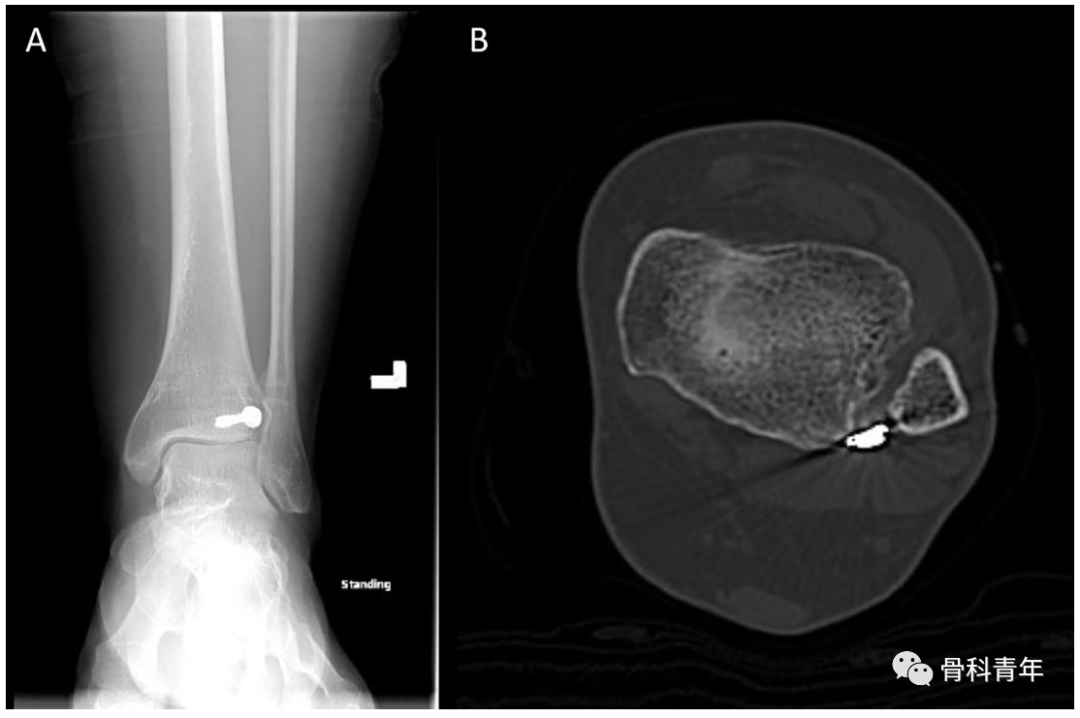

该例后踝螺钉穿入下胫腓的标本在CT横断中可明确。

依上述研究结果,在如下的后踝钢板固定中,透视钢板部分位于PVSL线外侧,有影响下胫腓风险,因此将钢板内移至PVSL线内

图中白色虚线即为PVSL线。